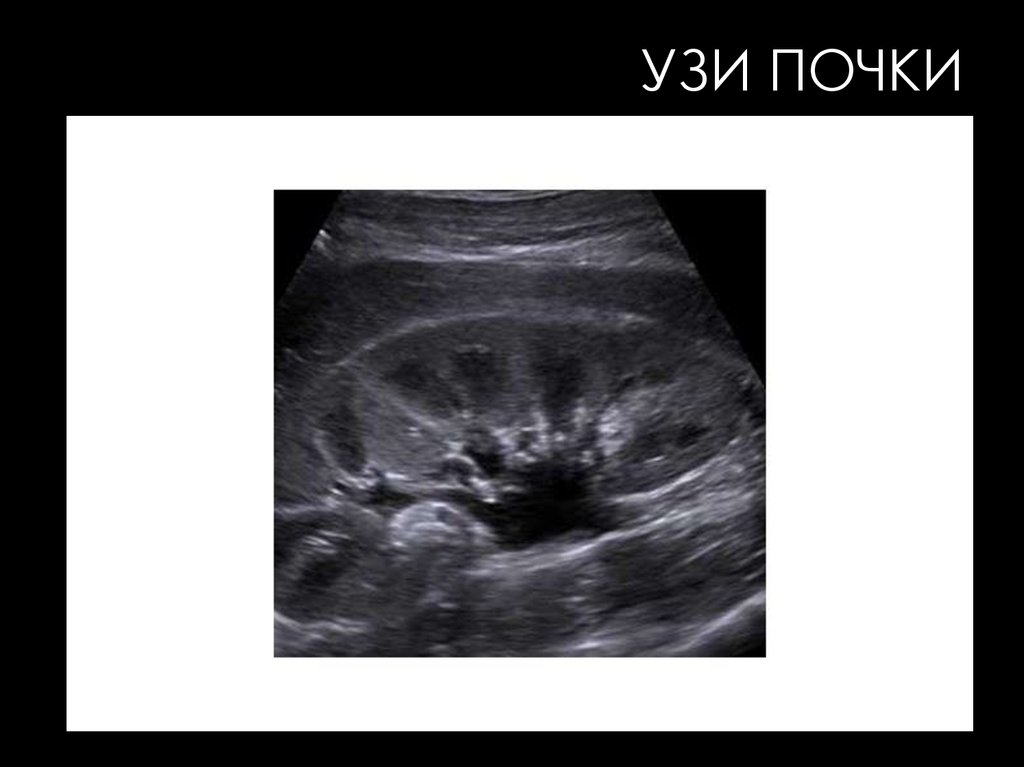

УЗИ ПОЧКИ

УЗИ ПОЧЕК

• Периферическая зона на эхограммах почек является

отображением паренхимы низкой эхогенности.

• Центральная зона почек является суммарным

отображением всех элементов почечного синуса. Его

высокая общая эхогенность обусловлена жировой

клетчаткой.